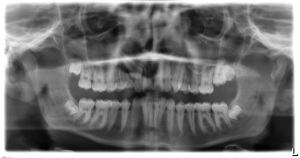

Röntgenbilder zur Übersichtsdarstellung aller Zähne und Zahnanlagen (OPG)